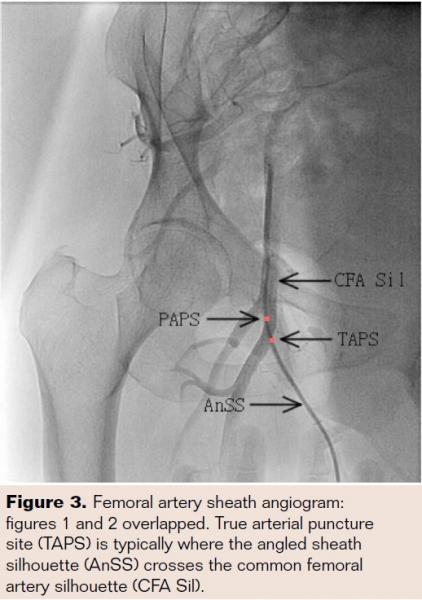

Introduction: Angiography is often performed following femoral arterial access for catheter-based procedures typically with the sheath angled away medially to determine the arterial puncture site location. This information is factored into decisions regarding deployment of a closure device. We hypothesized that determining the puncture site using the above technique may be inaccurate. Methods: We retrospectively analyzed 200 baseline femoral sheath angiograms (FSA) in a 35-degree ipsilateral oblique view with sheath angled medially away from the common femoral artery (CFA). The standard of care at our facility is to perform imaging using fluoroscopic subtraction angiography (“roadmapping”) capturing a contrast-filled Mynx balloon (MB; AccessClosure, Inc.) as it is withdrawn to the true arterial puncture site (TAPS) during closure device deployment. Three independent operators, blinded to MB images, were asked to mark the perceived arterial puncture site (PAPS) on baseline angiograms. The PAPS was then compared with TAPS (the center of the MB margin abutting the vessel wall), and the distance between the two points was measured. Results: TAPS was >3 mm caudad to PAPS in >80% of patients. Incidentally TAPS determined in this fashion correlates to the site where the angled sheath silhouette crosses the CFA silhouette. Conclusion: Commonly used techniques for isolating TAPS are often imprecise. When making decisions regarding closure devices, operators must be mindful of the fact that TAPS is often significantly lower than PAPS. Incidentally, a useful indicator of TAPS is the point where the angled sheath silhouette crosses the CFA silhouette in a 35-degree ipsilateral oblique view FSA.

After obtaining institutional review board approval, we retrospectively analyzed 200 consecutive studies and made a set of three hard copies (HC 1A, 1B, 1C) of the baseline FSA (Figure 1), which were printed and distributed to three independent observers to pinpoint with a sharp ball point pen the PAPS. A second hard copy (HC2) of the saved roadmap FSA with the MB withdrawn to TAPS was also printed (Figure 2). TAPS was pinpointed with a pen on HC2. The TAPS was depicted by a point on the horizontal line traversing the center of the MB where the line crossed the medial border of the CFA silhouette. The three PAPS hard copies (HC 1A, 1B, and 1C) were then sequentially placed on top of the TAPS hard copy (HC2) in a successive fashion, and each time the PAPS was projected from HC 1 A, 1B, and 1C onto HC2 with a pen. These 3 PAPS were labelled A, B, and C on HC2 (hard copy of the TAPS). If PAPS marked by two different independent observers were within .5 mm of each other they were considered to be one PAPS. Additional horizontal lines were then drawn through PAPS A, B, and C on HC2, which already had the horizontal line depicting TAPS on it. The vertical distance between each horizontal line depicting PAPS A, B, and C and the horizontal line depicting TAPS in the same patient, was then measured and carefully catalogued for final calculations.

Femoral artery angiograms of 200 consecutive patients with Mynx VCD usage were analyzed in this study. Patient demographics are tabulated in Table 1. One hundred and eleven patients (56%) were male, and the mean weight was 83.8 kg. The mean distance for the entire cohort of TAPS being caudad to PAPS was 4.4 mm ± 1.7 mm. Only 18.8% of patients demonstrated a TAPS to PAPS caudad difference of <3 mm, while 81.2% demonstrated the TAPS to PAPS caudad distance to be >3 mm. In 30.4% of patients, the TAPS was as far as 5 mm or more caudad to the PAPS (Table 2). Incidentally, in 97% of patients, TAPS is exactly the point where the angled sheath silhouette crosses the CFA silhouette in a 35-degree ipsilateral oblique view FSA. In spite of TAPS almost always being caudad to PAPS, there were no significant clinical adverse events noted in the first 30 days of follow-up, which may be attributable to the fact that the Mynx VCD used in all cases in this study is totally extravascular and is known not to negatively impact low CFA bifurcation sticks. In 15% of cases the operators identified a “low stick;” or perceived to be below the CFA bifurcation, and in the remaining 85% of cases, operators perceived the sticks to be above the bifurcation. Among these 85%, we did not routinely analyze the position of TAPS in relation to the CFA bifurcation to obtain an exact percent of patients in whom PAPS was felt to be “safe,” or above the bifurcation, but TAPS was in fact below.